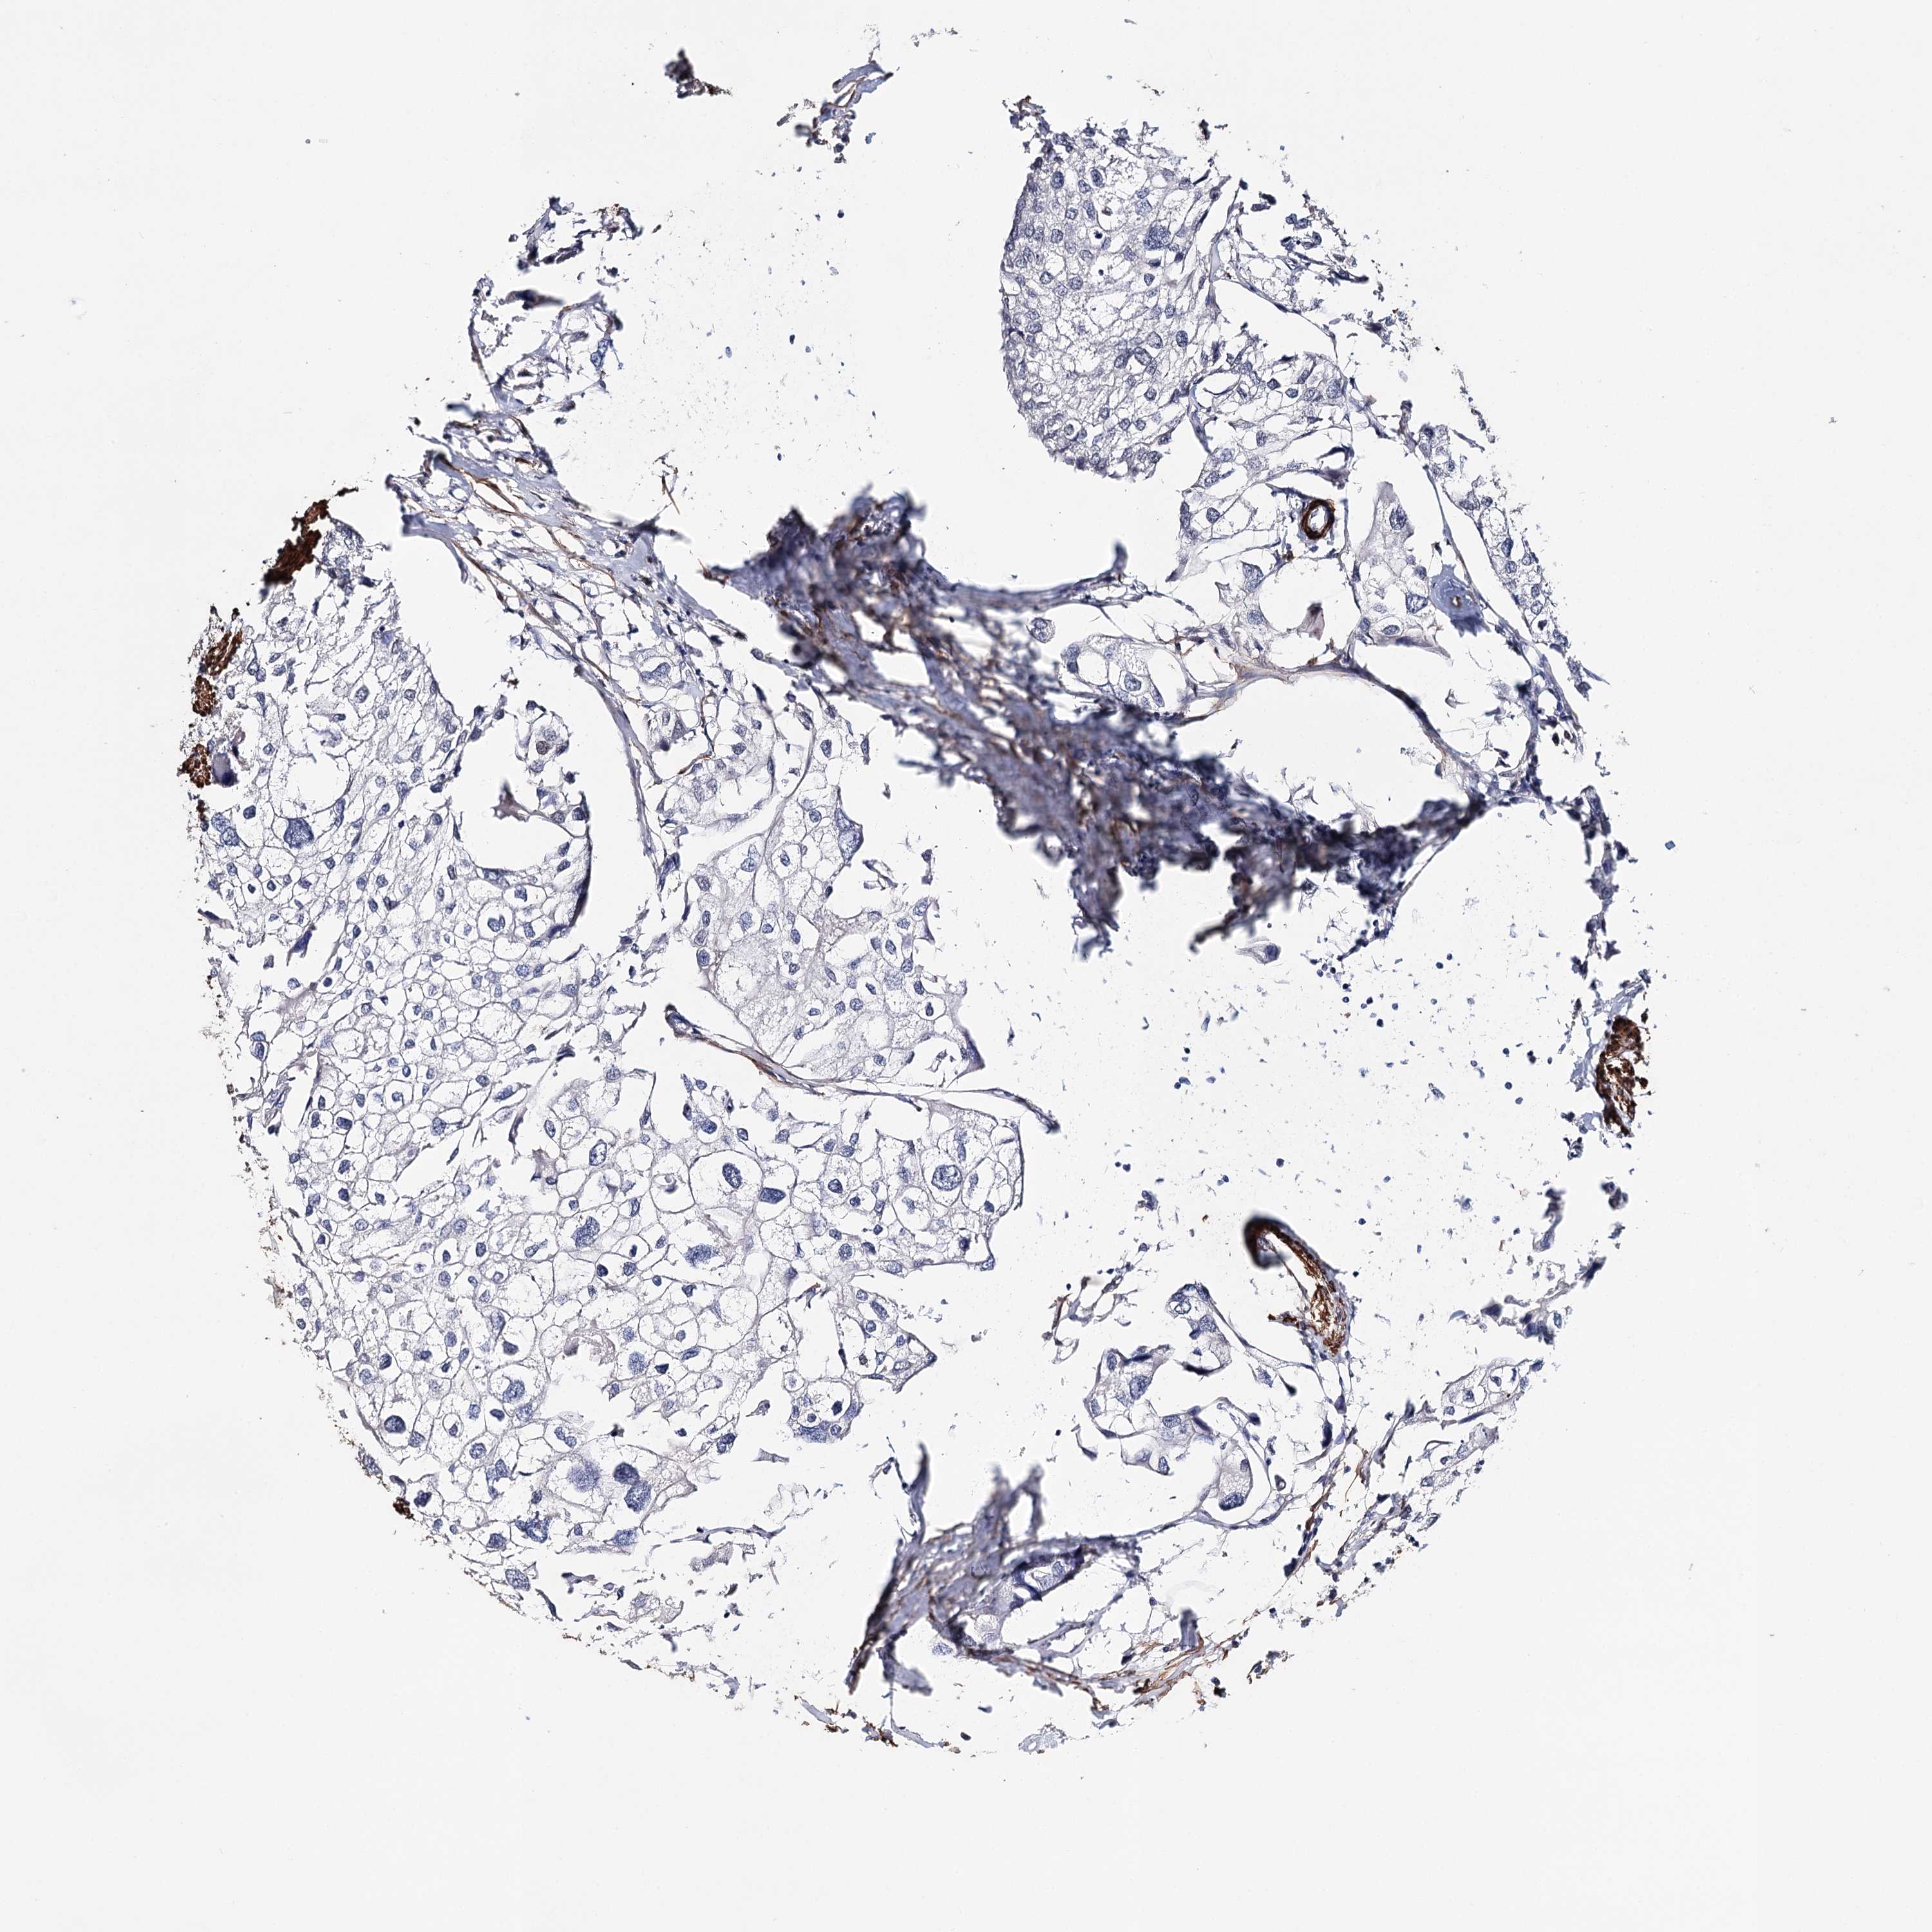

UROTHELIAL CANCER - Protein expressioni

A mouse-over function shows sample information and annotation data. Click on an image to view it in a full screen mode. Samples can be filtered based on level of antibody staining by selecting one or several of the following categories: high, medium, low and not detected. The assay and annotation is described here.

Note that samples used for immunohistochemistry by the Human Protein Atlas do not correspond to samples in the TCGA dataset.

Antibody stainingi

Antibody staining in the annotated cell types in the current human tissue is reported as not detected, low, medium, or high, based on conventional immunohistochemistry profiling in selected tissues. This score is based on the combination of the staining intensity and fraction of stained cells.

Each image is clickable and will lead to virtual microscopy that enables deeper exploration of all samples and also displays staining intensity scores, fraction scores and subcellular localization as well as patient and tissue information for each sample.

Antibody HPA037786

Antibody HPA038034

Antibody HPA038867

Antibody HPA038868

Staining

High

Medium

Low

Not detected

Intensity

Strong

Moderate

Weak

Negative

Quantity

>75%

75%-25%

<25%

None

Location

Nuclear

Cytoplasmic/membranous

Cytoplasmic/membranous,nuclear

Urothelial carcinoma, High grade

Urothelial carcinoma, Low grade

Urothelial carcinoma, NOS